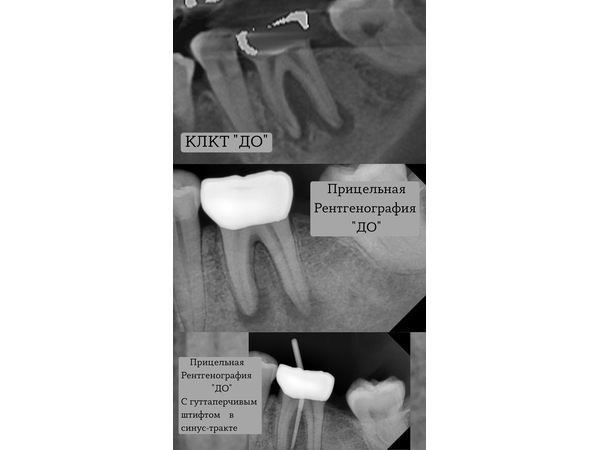

По результатам КТ, в области разделения корней, а также вокруг верхушек корней плотность кости снижена. Кроме этого, наблюдается разрушение кортикальной пластинки (плотного верхнего слоя кости).

На рентгенограмме за такой короткий срок особых изменений не заметно. Но отсутствия жалоб и симптоматики достаточно, чтобы считать проведённое лечение успешным и в этот же день продолжить выбранную тактику.

На рентгенограмме через 6 месяцев было видно, что костная ткань восстановилась и периодонт практически здоров, т. е. цель лечения была достигнута.